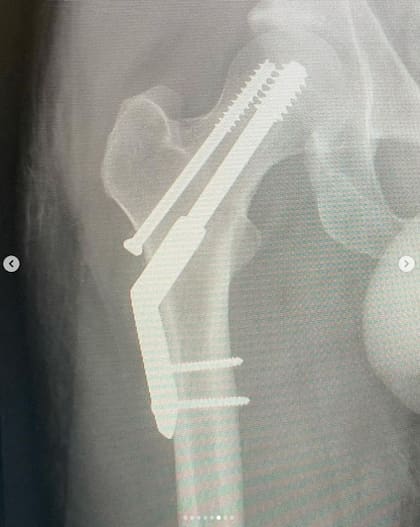

El cantante australiano compartió su posteo con una serie de imágenes desde que llegó a la institución donde lo atendieron hasta las radiografías de la cirugía, con los tornillos que colocaron en su fémur, y también la sutura que hora tiene en su pierna derecha. Además, circuló un vídeo en el que se lo ve subiendo una escalera, acompañado por una asistente, en plan de rehabilitación.

“Me fracturé la cadera -dice su posteo en Instagram-. Traté de correr una media maratón y eso resultó en una fractura por estrés. ¡Vaya! Llegué a menos de 1 kilómetro de la línea de meta. Así es la vida, supongo. Todos los shows en México y América del Sur se llevarán a cabo según lo planeado. No voy a renunciar a ustedes”, escribió el frontman de la banda en Instagram.